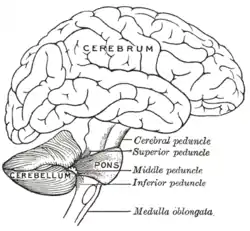

Scheme showing the connections of the several parts of the brain. (Inferior peduncle labeled at bottom right.) | |

The juxtarestiform body is a subdivision of the inferior cerebellar peduncle, which comprises both the juxtarestiform and restiform bodies.

The juxtarestiform body carries both afferent and efferent fibers connecting the vestibular nuclei and the flocculonodular lobe and fastigial nucleus of the cerebellum.

The juxtarestiform body coordinates balance and eye movements by communication between the vestibular apparatus and the cerebellum.